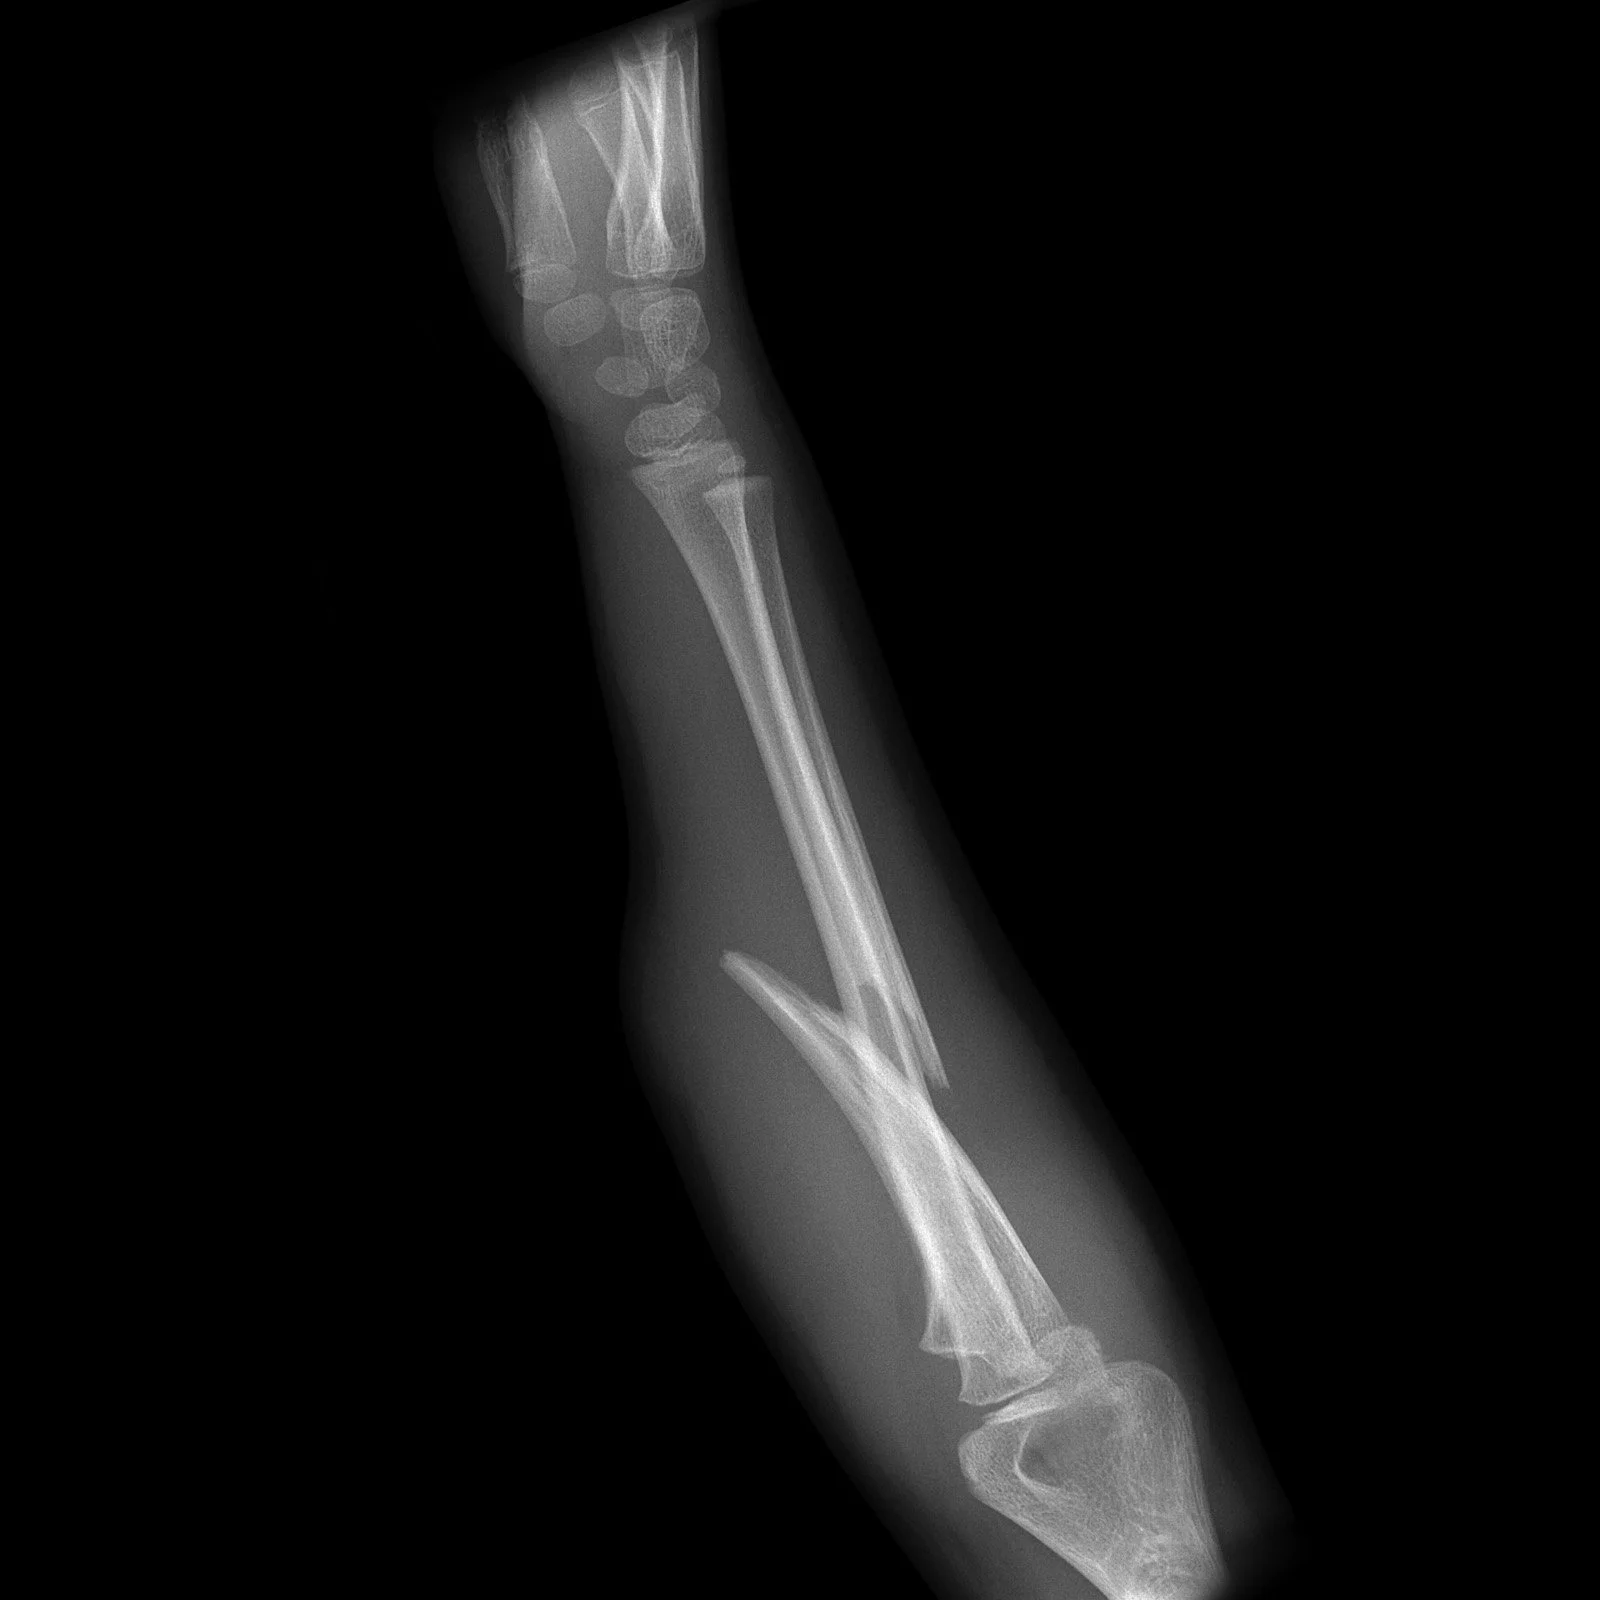

Chauffeur fracture

• Intra-articular fracture of radial styloid process.

• Associated with scaphoid-lunate dissociation.

Case courtesy of Henry Knipe, Radiopaedia.org, rID: 46624 (Chauffeur case)